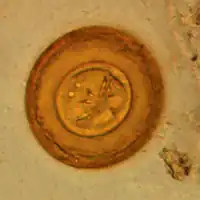

La oncosfera o hexacanto es un estado larvario de los cestodos. Esta larva es ciliada, esférica, y está provista de tres pares de ganchos; se encuentra contenida en la envoltura embrionaria externa del huevo.[1][2][3]​ Es el primer estado diferenciado en los ciclofilídeos. El conjunto de la oncosfera y el embrióforo se denomina coracidio.[4]